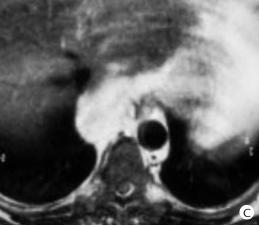

Image TDM : Masse homogene de

densite tissulire , non calcifie , hypervasculaire

et hyper T2 heterogene |